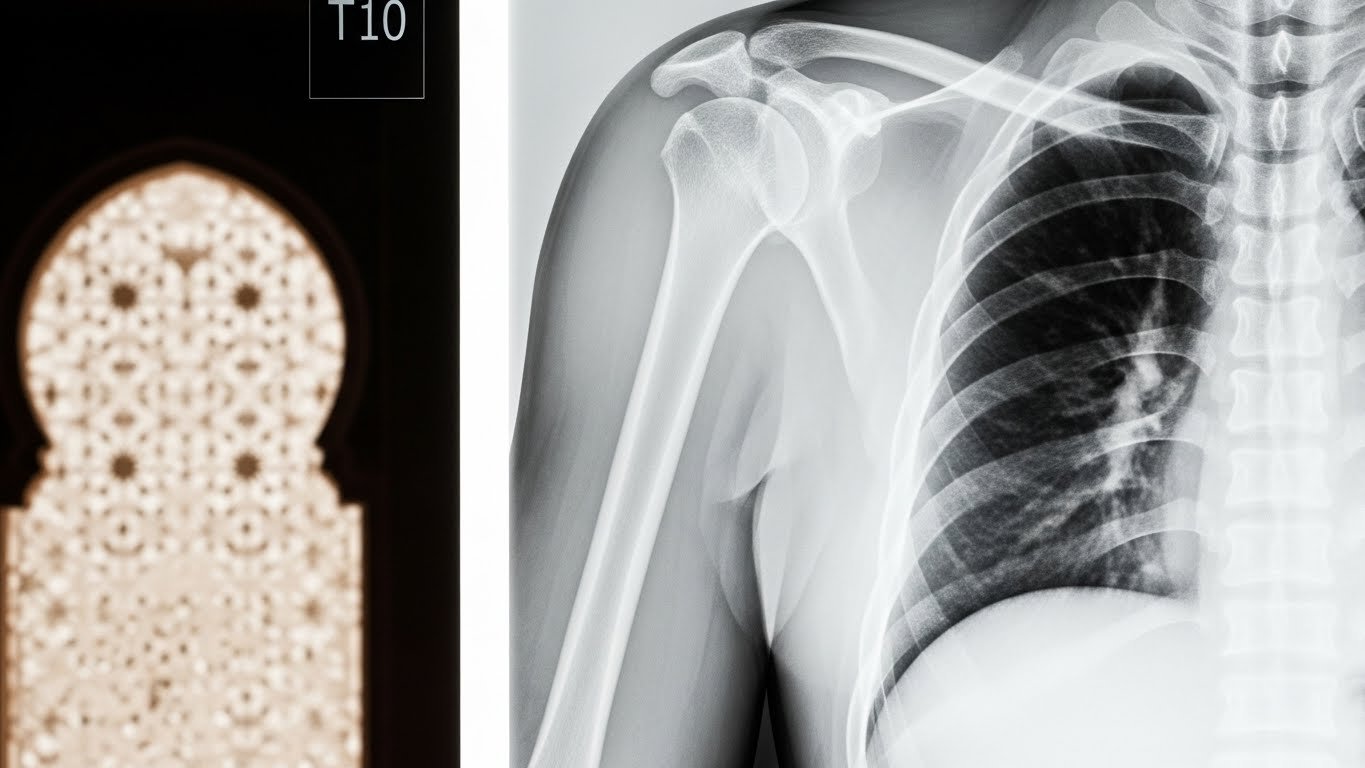

La radiographie du rachis dorsal est une technique d’imagerie médicale qui utilise les rayons X pour obtenir des images de votre colonne vertébrale au niveau du dos. Plus précisément, elle photographie la zone située entre votre cou et vos lombaires (le bas du dos).

Cette partie de la colonne, appelée aussi rachis thoracique, est composée de 12 vertèbres numérotées de D1 (ou T1) à D12 (ou T12). Ces vertèbres sont particulières car elles sont reliées aux côtes, formant ainsi la cage thoracique qui protège vos organes vitaux.

Une radiographie du rachis dorsal complète nécessite habituellement deux clichés minimum : un de face et un de profil. Ces différentes vues permettent au radiologue d’obtenir une vision tridimensionnelle de votre colonne.

Point technique important : Cette incidence est cruciale car elle permet de visualiser :

• L’alignement de vos vertèbres les unes par rapport aux autres

• La hauteur de vos disques intervertébraux

• Les courbures naturelles de votre colonne (cyphose thoracique)

• D’éventuels tassements vertébraux